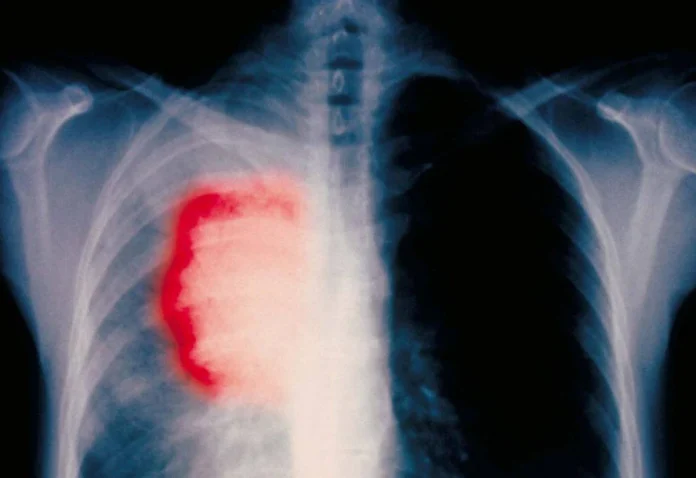

Una proteína llamada isocitrato deshidrogenasa (IDH1) está presente en altos niveles en los cánceres de pulmón y puede ser detectado en la sangre, por lo que es un marcador de diagnóstico no invasivo del cáncer de pulmón, según un estudio publicado en Clinical Cancer Research, una revista de la Asociación Americana para la Investigación del Cáncer.

El cáncer de pulmón es la principal causa de muerte por cáncer en hombres y mujeres en los Estados Unidos y en todo el mundo. Para detectar el cáncer de pulmón en la sangre , se utilizan actualmente ciertos biomarcadores incluyendo CEA , CYFRA21-1 y CA125 , pero estos marcadores no son muy sensibles , de acuerdo con él.